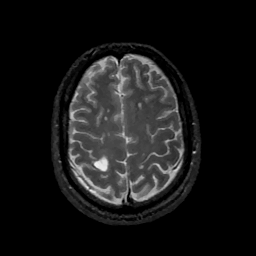

MR Study #11, May 5, 1991 -- Slice #39

[Home][Help][Clinical][Tour 1][Tour 2] Slice 39